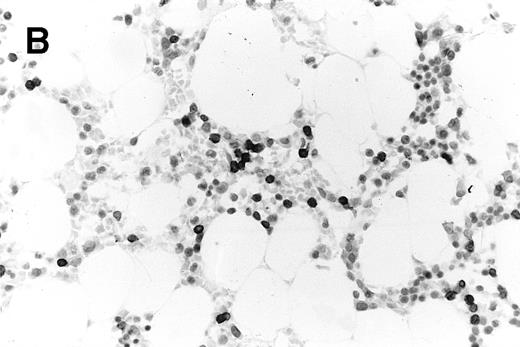

In 39 patients there was concordance between the PET scan and the routine iliac crest marrow biopsy (Table1). In 26 patients there was no increased FDG uptake within the marrow and the biopsy histology was normal. In 13 patients increased marrow FDG uptake was associated with histological evidence of marrow infiltration by lymphoma in the routine iliac crest biopsy (11 NHL, 2 HD). Two of these patients demonstrated the sensitivity of the PET technique: 1 patient with follicular centroblastic centrocytic lymphoma who had low-volume, nodular marrow disease (Fig 3A) and another patient with T-lymphoblastic lymphoma, who had only 15% blast cells on marrow aspirate and a modest interstitial infiltrate on trephine section (Fig3B). Both had the marrow disease identified by increased FDG uptake. Only 1 of the 5 patients with focal FDG uptake in an otherwise normal marrow had, by chance, an area of high FDG accumulation (“hot spot”) biopsied by the routine marrow trephine, which confirmed NHL.

Trephine biopsy sections. (A) A patient with follicular centroblastic centrocytic lymphoma stained with hematoxylin and eosin showing low-volume, nodular disease (original magnification ×100). (B) A patient with T-lymphoblastic lymphoma stained with anti-CD3; cells with dark cytoplasm are CD3+ (original magnification ×400). These photomicrographs show the low level of lymphoma infiltration which in both cases was detected by PET.